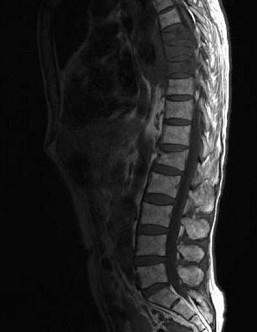

问题 椎管内肿瘤(如图所示)的特征性表现是()

选项 A.神经根痛表现为夜间疼痛或平卧痛加重 B.脊髓半切综合征 C.平面以下完全性肢体瘫痪 D.平面以下感觉障碍 E.自主神经功能障碍

答案 A